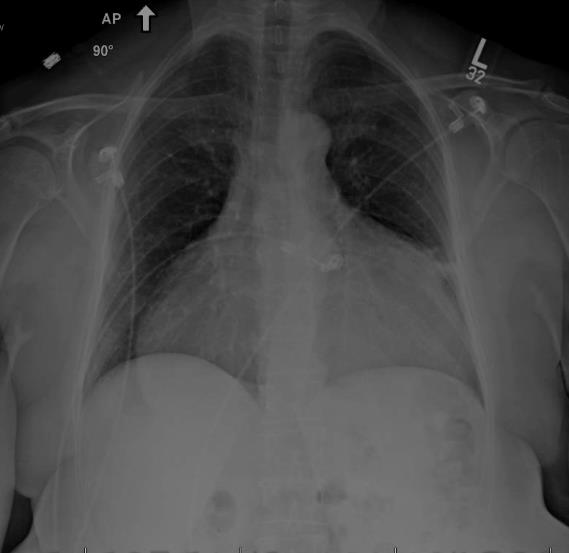

A 58-year-old woman presented with a symptomatic, massive pericardial effusion. Due to shortness of breath for over three months, she underwent percutaneous pericardial drainage (Fig. 1). She had no other significant medical problems.

1.5 liters of serous, odorless fluid was removed and the echo appearance normalized, showing only trace pericardial fluid and a well-preserved ejection fraction. However, within four weeks the effusion re-accumulated as shown in the CXR (Fig.2) and echo showed early tamponade.